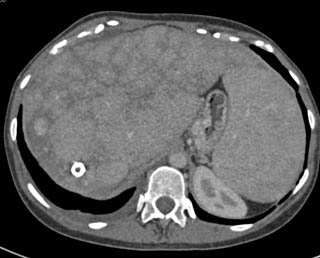

In this patient with Budd Chiari the enhancing liver nodule is most likely?

hepatoma

hepatic adenomas

fibrolamellar HCC

regenerating nodule